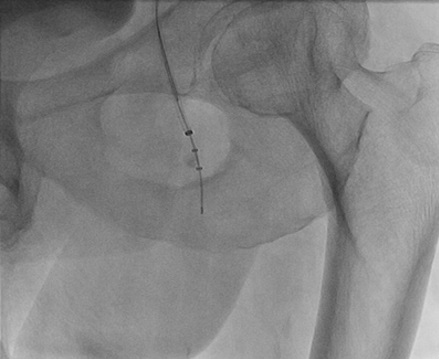

A 71-year-old retired veteran presented with a chronic RCA CTO.  He underwent RCA stenting 15 years ago, and had a previously placed AV sequential pacer.  He underwent attempted CTO treatment via the right femoral artery with sheath placement of the left groin for possible Impella placement or retrograde approach.  We used an 8 French JR4 guiding catheter and placed a .014 Miracle 3 wire through a FineCross through the CrossLock™ catheter.  With the CrossLock™ balloon dilated and centering our position in the vessel, we quickly traversed the CTO with the wire and the FineCross.  The Fielder XT was then used, but we were not able to advance further so we switched to a Whisper wire and advanced to the mid portion of the RCA.  The FineCross was not able to be advanced, and we switched to the Caravel microcatheter.  With further passage of the CrossLock™ and with the Caravel’s support, we successfully placed drug eluting stents to complete the procedure.

Figure 1. A right coronary angiogram performed with an 8 French JR4 guiding catheter.

Figure 2. The CrossLock™ is in place at the origin of the RCA.

Figure 3. Utilizing the firm support with the CrossLock™ and with no pressure applied with a stiff guiding catheter, we were able to pass into the CTO. Note the miracle 3 wire is inside a FineCross catheter.